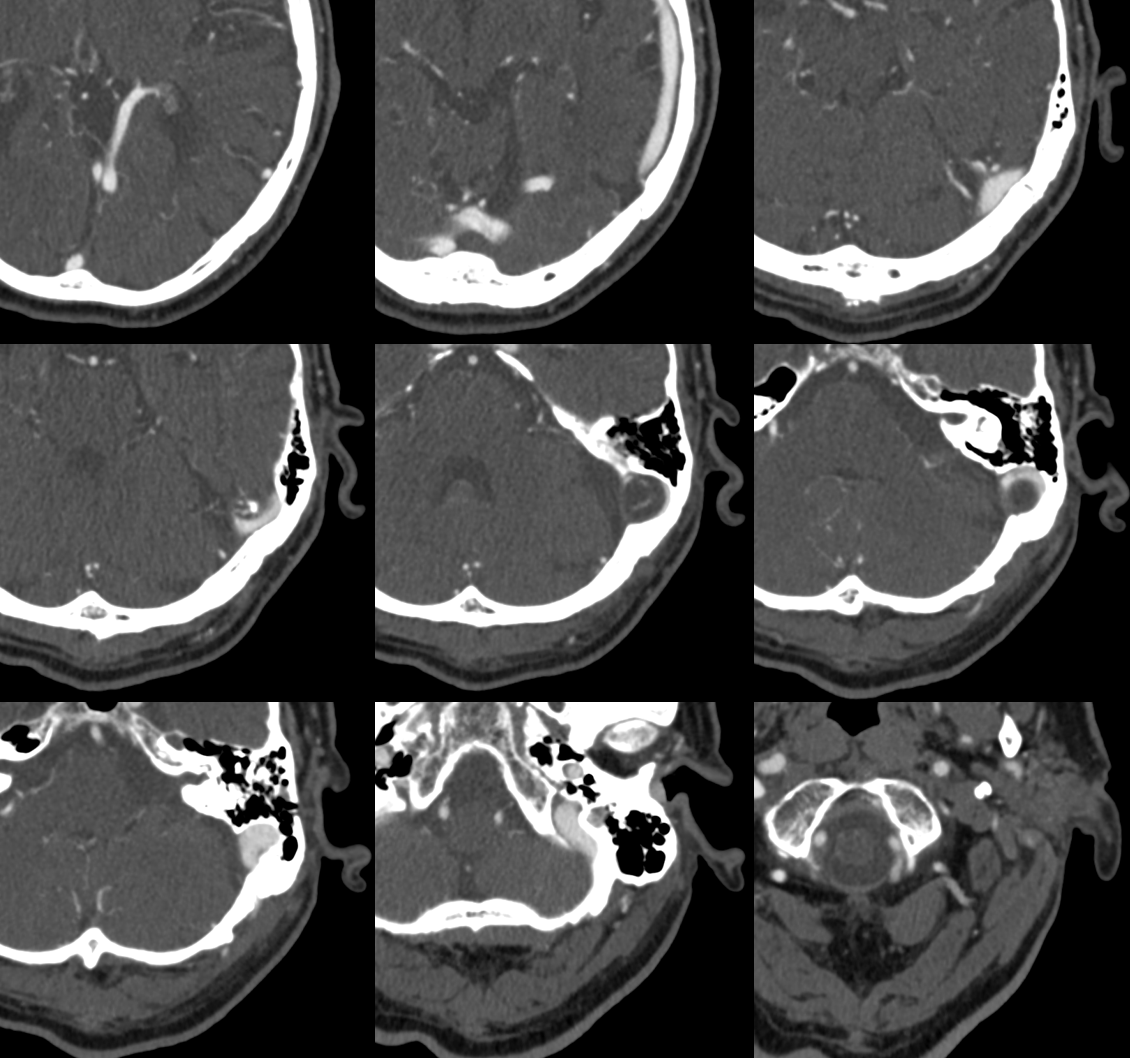

All of the above anatomic knowledge can become very useful in evaluation of venous thrombosis. Numerous collateral pathways develop in this setting attempting to compensate for the loss. The most dramatic cases usually involve the largest channel — the superior sagittal sinus. In this case, a man presented with what initially was thought to be vasculitis-related brain hemorrhage. Subsequent workup led to an angiogram, where sagittal sinus thrombosis with extensive trans-cerebral and trans-osseous emissary vein collateral channels was seen. In retrospect, these findings were present on the patient’s earlier contrast MRI. “Venovibe” or other contrast-enhanced MR venograms can very sensitive, particularly when interpreted with the appropriate index of suspicion. Noncontrast 2-D time of flight MRV I consider to be next to useless as a problem-solving technique. Any thin-slice postcontrast T1 study is vastly superior.

NOT ALWAYS ASYMPTOMATIC! — here is left frontal convexity cortical venous thrombosis in veins emptying into SSS at level of giant granulation. Very likely related. Granulation is in middle upper row image. Full case (angios etc) here.